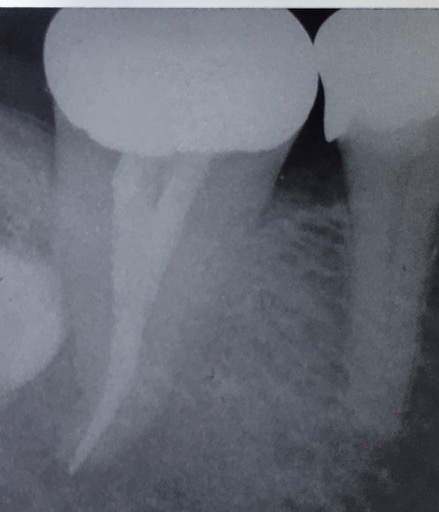

An X-ray of a lower molar tooth with a white line inside the root indicating a root fillinga root filling